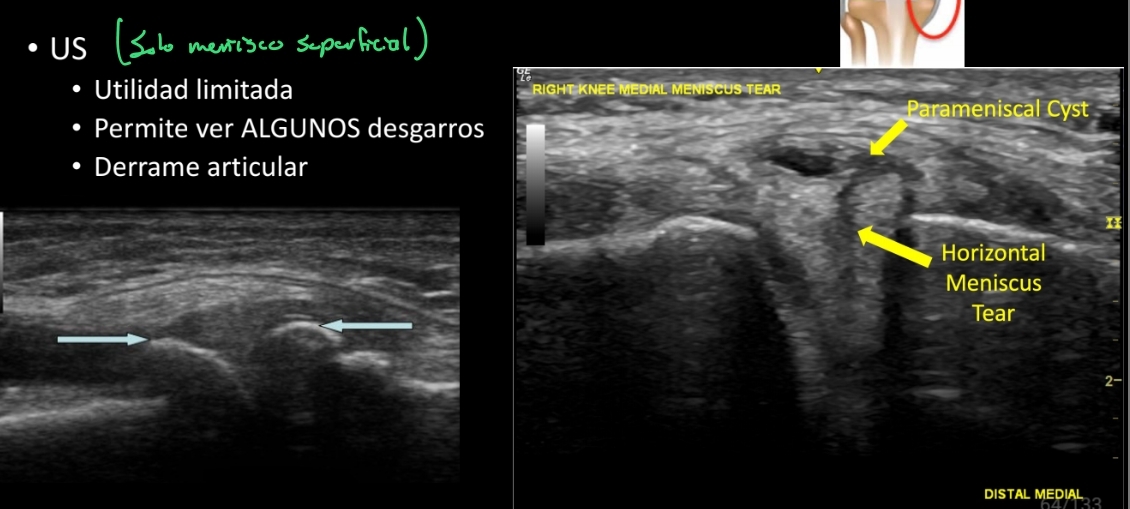

12

Q

Qué se ve en un US en un desgarro meniscal?

A

• Solo se ven algunos desgarros = utilidad limitada

• Se pude ver un derrame articular

How well did you know this?